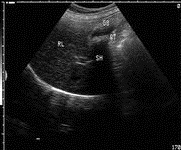

胆囊结石漏诊的原因: 胆囊颈部结石;特殊类型的胆囊结石,超声表现不典型,如泥沙样结石、充满型结石;或由于胆囊萎缩导致显示不清;伪像干扰;仪器调节不当等等; 误诊原因有:胆泥、胆汁粘稠、胆囊壁息肉、胆囊壁颈部褶皱、血凝块、胆囊内气体、药物性胆囊结石等; 如何提高超声诊断正确率?

熟悉胆道系统超声解剖,包括胆囊和胆管的超声解剖;

正确认识上述提到的漏诊与误诊原因;

提高检查手法,能针对不同的胆道解剖结构,采用不同超声显示切面